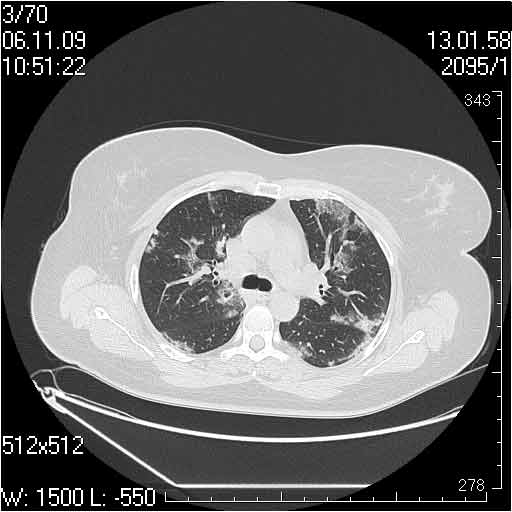

Случай №3

Женщина 51 год

Случай 3:смешанные изменения; подходят для интерстициальной пневмонии, тактика аналогична случаю 1.